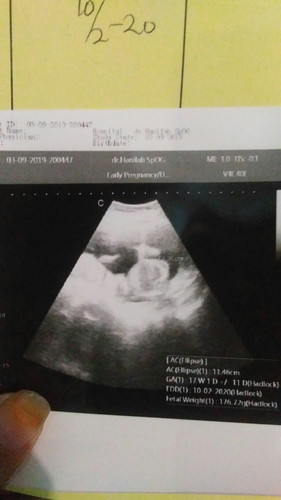

hasil usg

Bun ini hasil usgku, alhamdulilah dd nya sehat normal. Tp kok di hasil Ny 17week1D, Di bidan 16week5d yak.yg bnr yg mna bun? Mhon infonya dong. Hasilnya jg d kertas Belum jelas bgt. Tp Di komputer udh kelihatan dn lg gerak2 tdi.ada yg sma kah hasil 17week kya gni